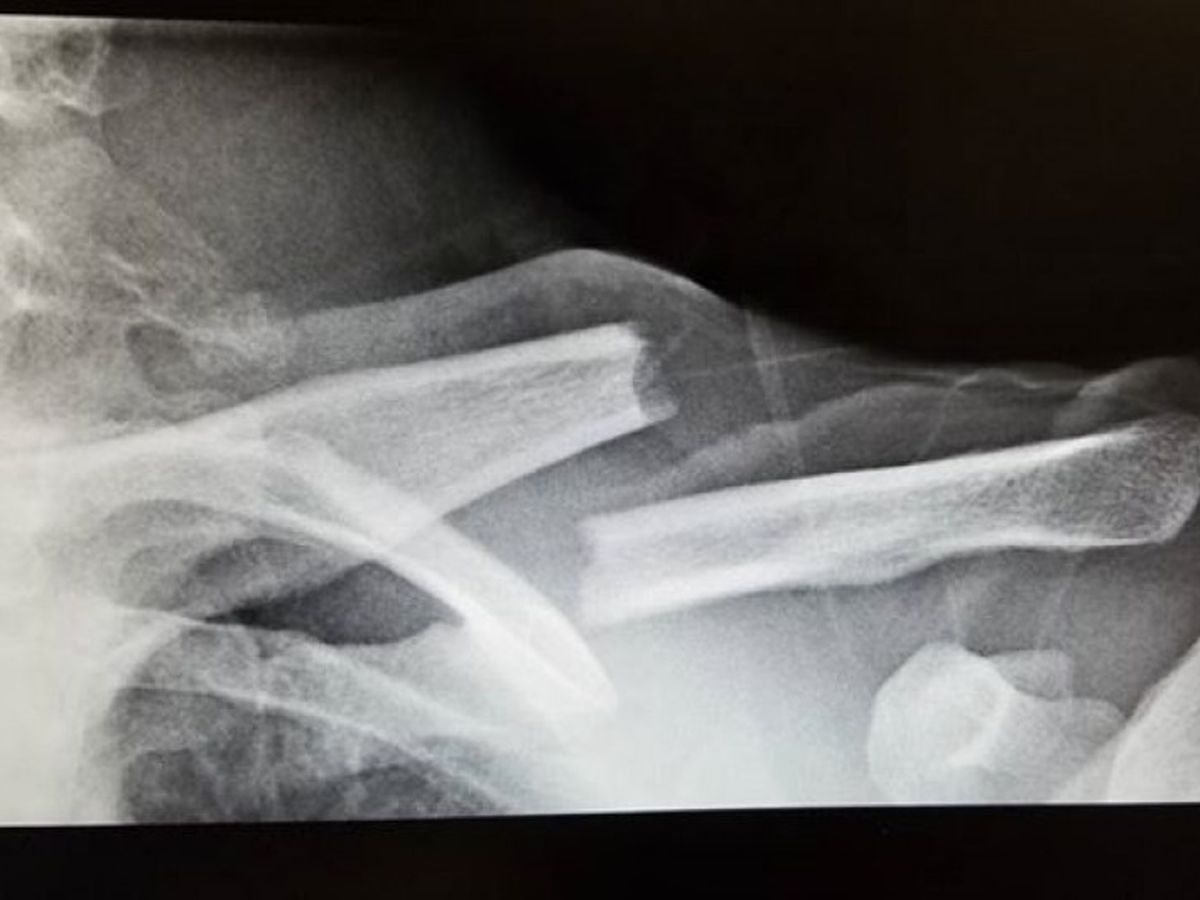

Martin lost his 20 month old son, Ryan, and his 5-year girlfriend, Cristina Mier, in a car accident on July 7, 2017. They were beautiful and full of life. Martin went through the windshield on the passenger side and suffered severe injuries, yet got up and tried to rescue his family from the vehicle. He has a head injury, broken neck, broken ribs, lacerated internal organs, and he was impaled by debris from the accident that broke his clavicle and went deep into his neck. Along with these and many other lacerations and bruises, Martin is suffering from post traumatic stress as a result of witnessing the horrific events of his family passing away in the accident. His clavicle injury could not be fully repaired in the hospital due to the severity of his other injuries. His health insurance is minimal and multiple attempts to get Marty seen by a surgeon and approved by insurance for the surgery needed to repair his clavicle and restore full use of his arm have failed. He is currently relying on family for support, but Marty will need long term physical and mental health treatment in order to recover. We are raising money to pay for his surgery and other medical and living expenses he will have on his long road to healing. Thank you for you help!